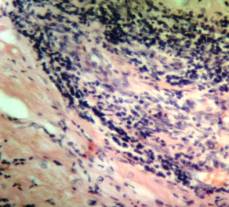

2.

Микрофотография опухолевой инфильтрации миокарда

Результаты

патогистологического исследования следующие: лимфоузлы ткани яичка —

неходжкинская лимфобластная лимфома; миокард правого желудочка и правого

предсердия — инфильтрация лимфобластная с очаговыми некрозами; легкие —